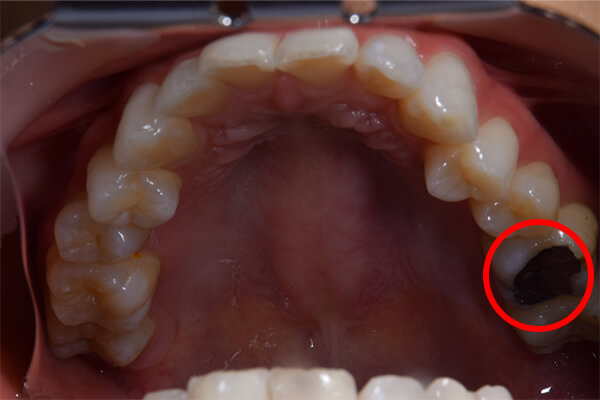

「左上の奥歯に違和感がある」という悩みを持たれている患者様が来院されました。虫歯部分を除去すると歯の神経に届いていましたので、歯の神経を守るために根管治療を行いました。

他院で診てもらったが腫れや痛みが変わらないとのことだったので、患歯を見極めることがまずは重要になります。今回は左上の前から5番目の歯が原因と判断しました。診断名は急性根尖性歯周炎。

初診時は腫れが大きかったので、膿を出すために歯茎を1センチ弱切り、中の膿をだしました。2回目の治療から、感染根管処置を行います。根管洗浄と機械的清掃です。治療後は3ヶ月経過を見て、再発がないかを確認します。問題なければかぶせ物をして終了です。

患歯を見極めるためと、状態の悪さをみるため、CTを撮影しました。治療前では上顎洞への大きな炎症が見られます。また、上顎洞底線も無くなっています。また左上の前から4番目の歯の根尖周囲にも透過像が見られます。5番目の歯に関しては根尖が鋭利になっており、根尖性歯周炎によって吸収されたことがわかります。ですので、まず第一の患歯は5番目の歯であるとしました。